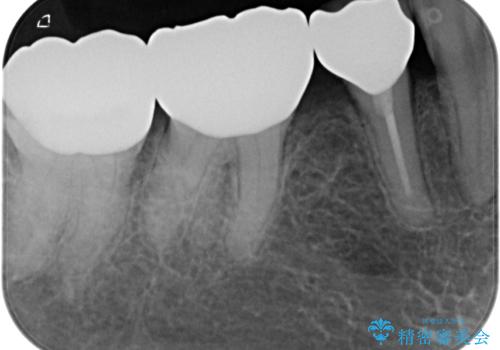

- 奥歯の目立つ銀歯と、神経が失活して変色した前歯を気にして来院された患者様です。

銀歯と歯の間に隙間があり、冷たいものがしみる知覚過敏の症状が認められたため、銀歯を白くするだけでなく、知覚過敏症状の改善も狙って補綴治療を行うこととしました。